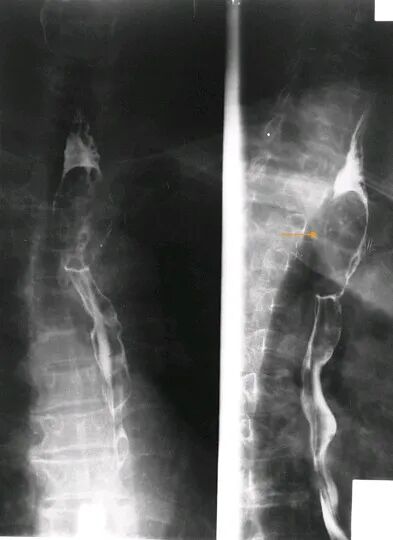

食管癌(增生型)

食管钡剂造影显示食管上段管腔内椭圆形充盈缺损,粘膜皱襞消失,管腔狭窄

食管癌